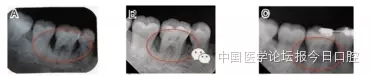

▲图8 16手术前后根尖片比较。A:16手术前(近中牙槽骨吸收近根尖),B:16手术后3个月(近中牙槽骨高度良好),C:16手术后2年(近中仍保持令人满意地牙槽骨高度)

▲图9 46手术前后根尖片比较。A:46手术前(近远中牙槽骨吸收至根长2/3),B:46手术后3个月(近远中牙槽骨高度良好),C:46手术后2年(近中牙槽嵴顶有少量骨吸收,远中牙槽骨高度良好)